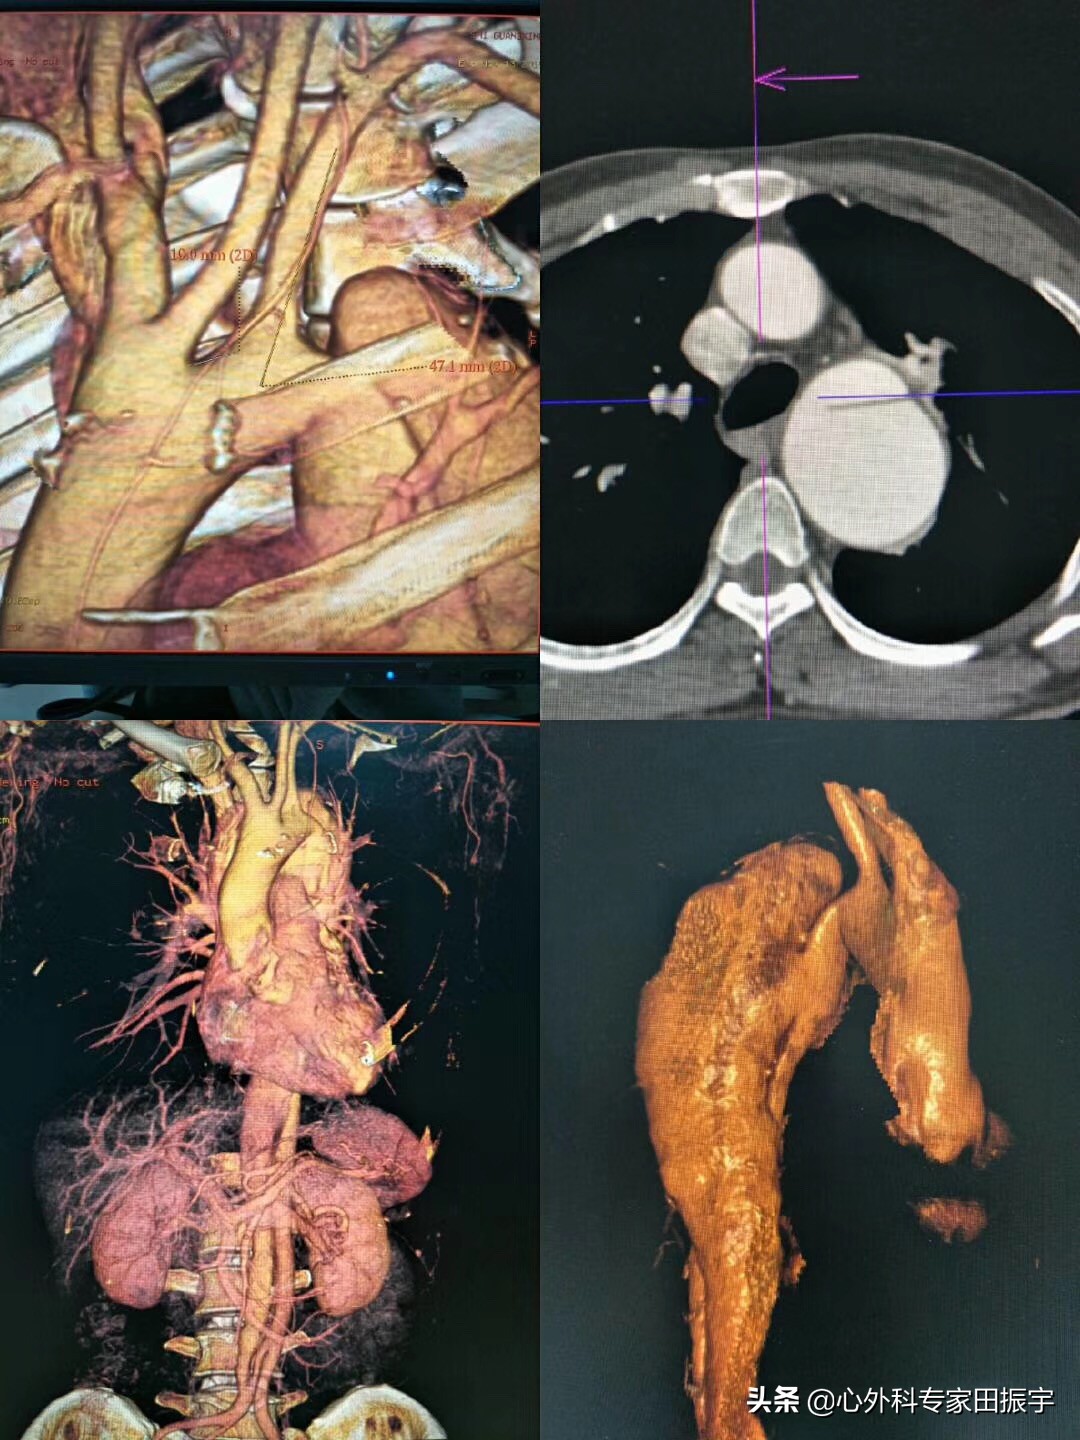

仔细的体格检查可能为主动脉瘤或夹层的严重程度提供线索。这必须包括大脑、心脏、脑和四肢的评估。接下来,进行心电图、胸部X光和适当的实验室研究(一类推荐,证据B)。在确诊主动脉夹层的高风险患者中,阴性胸部X射线不应延迟进一步的横截面成像(III类推荐,证据C)。计算机断层扫描(CT)一直是评估的支柱,提供治疗效果的细节和纵向监测和评估。为了获得最大的好处,计算机断层扫描血管造影(CTA)理想情况下应获得,这可能在所有患者中都是可能的。在 CTA 中,静脉对比以 3~5 mL/s 的速度传递,从颈部到腹股沟形成 3 mm 厚的主动脉图像切片。在多个级别(一类推荐,证据C),在主动脉根水平上,最大直径通常是主动脉窦中部水平,其直径最宽。此外,在CT扫描中,应注意存在主动脉壁间血肿(IMH)和穿透性动脉粥样硬化性溃疡(PAU)。磁共振成像 (MRI) 可以提供主动脉的卓越图像,但其使用不便导致临床较少应用于主动脉夹层的诊断。一旦诊断完成,经胸超声仍然是诊断有无心包和胸腔积液以及主动脉瓣有无关闭不全的主要检查。

主动脉CTA